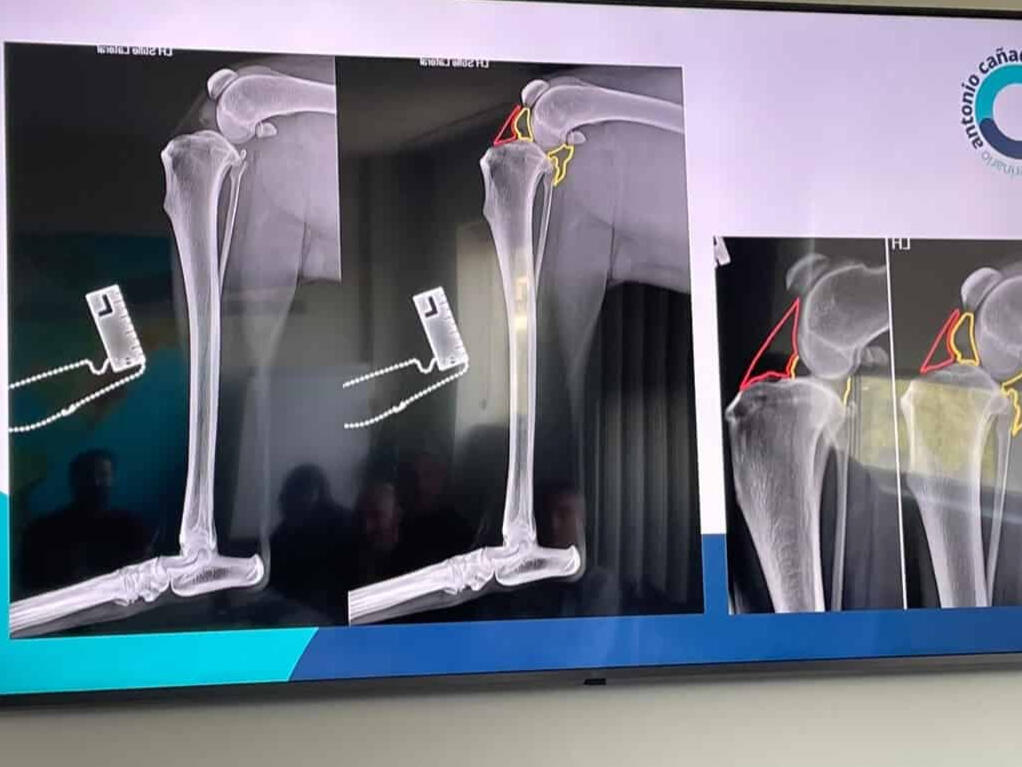

In addition, I continuously train in the areas of orthopedics, traumatology, and pain control. General and traumatological surgery.